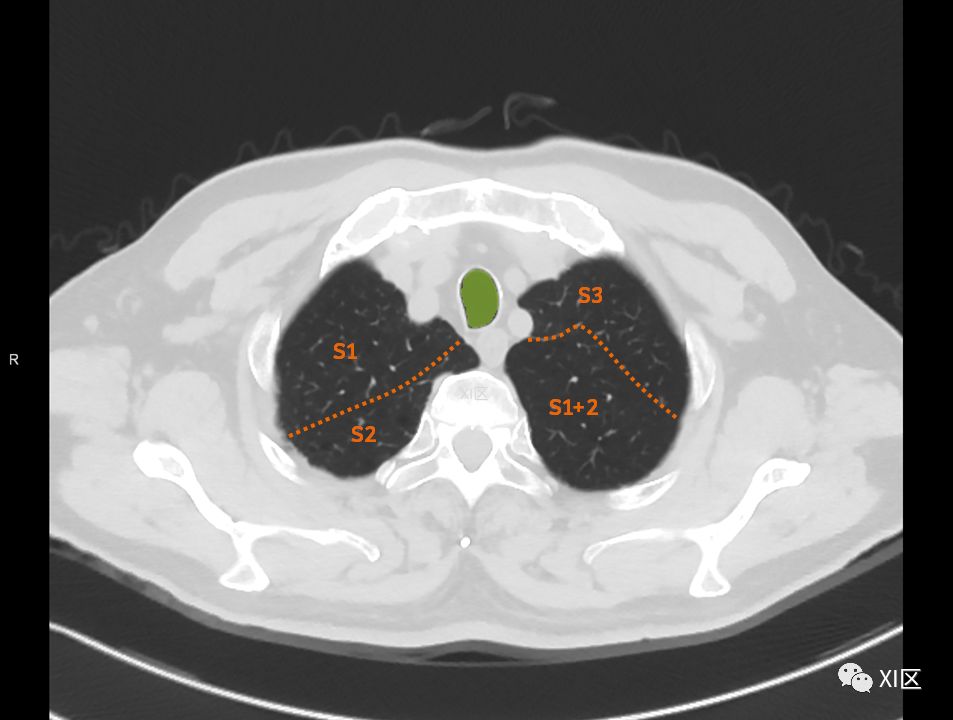

在进行肺的分段时,可以上下观察浏览,沿着相应气管的走形可以更容易准确地进行分段。

肺的断层分段示意图